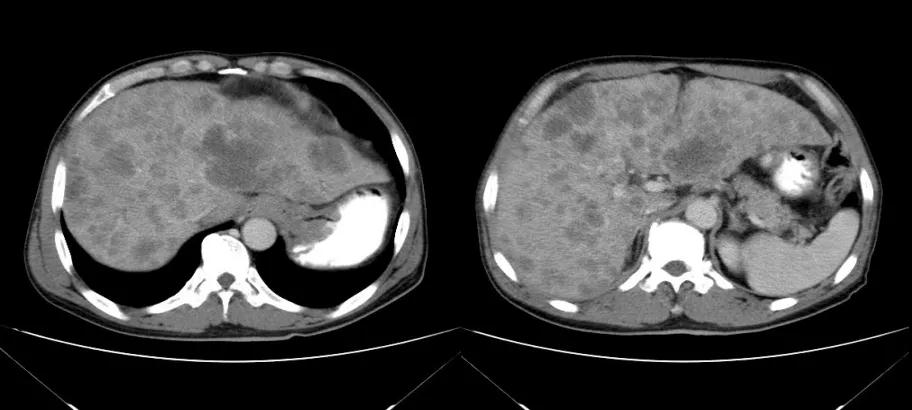

诊治经过:2020年12月16日患者行第二次经皮动脉化疗灌注栓塞术(铂类+氟尿嘧啶)治疗,并继续联合吡咯替尼治疗。结果见图3。

图3